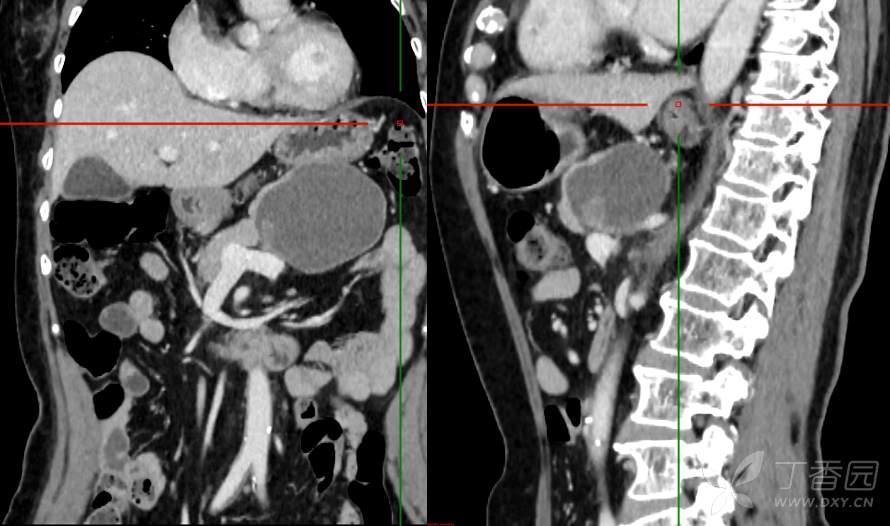

主 诉:发现胰腺占位性病变3月

现病史:患者3月前就诊于**市人民医院行腹部增强CT发现胰尾占位性病变,无腹痛、腹胀,无恶心呕吐,无黄疸,无呕血黑便,无胸闷憋气,无寒战高热,未行特殊治疗